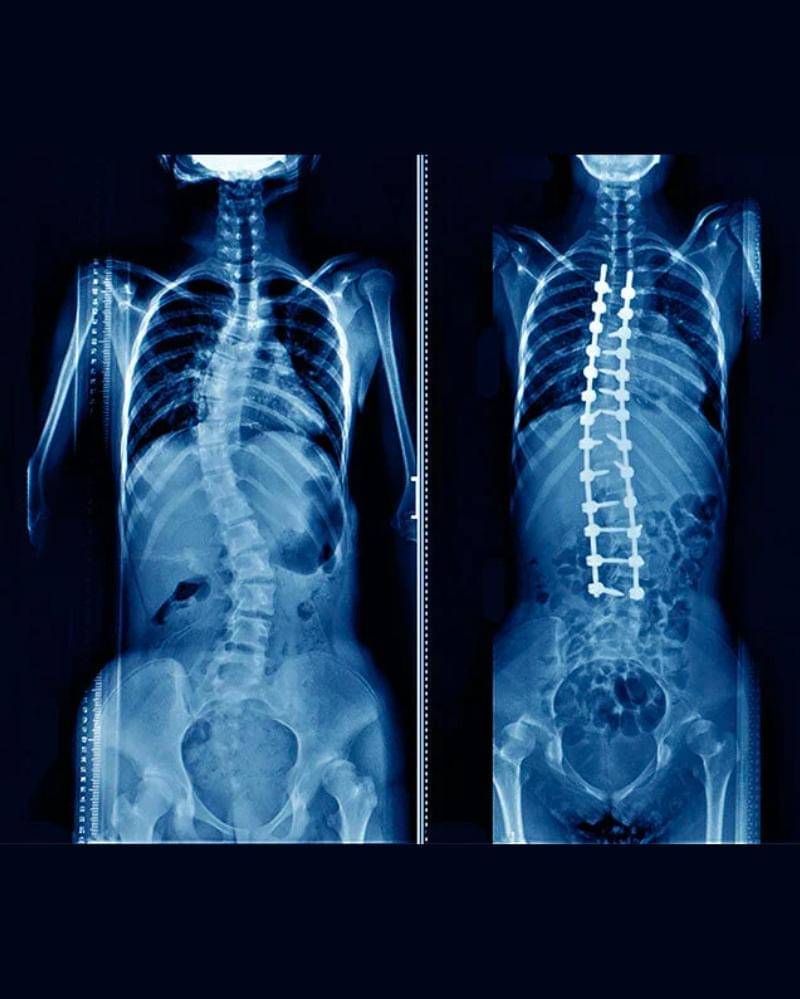

Skoliosis merupakan kelengkungan tulang belakang ke samping yang paling sering didiagnosis pada remaja. Meskipun skoliosis dapat terjadi pada orang dengan kondisi seperti palsi serebral dan distrofi otot, penyebab sebagian besar skoliosis pada masa kanak-kanak tidak diketahui.

Saat itu, dokter menyarankannya untuk menjalani operasi karena tingkat kelengkungan tulangnya mencapai 40 derajat, yang dianggap cukup parah.

Pada saat Gitarani memutuskan untuk operasi, tingkat kelengkungan tulang punggungnya telah mencapai 70 derajat, yang jika dibiarkan akan memberi tekanan pada paru-paru, jantung, dan organ pencernaan.